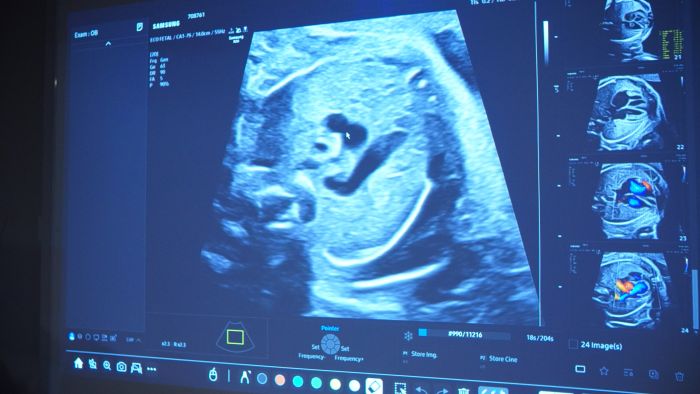

A agenda de gravações e exames da terça-feira (10/02) refletiu a versatilidade do novo aparelho na execução de casos de ultrassonografia diversos, como o Exame Arterial, realizado pelos Profs. Procópio e Jorge Garcia, o Exame Obstétrico, sob o olhar da Profa. Daniela Barra, o Exame Abdominal, com o Prof. Augusto, e o Exame Venoso, também com os Profs. Procópio e Jorge Garcia. A programação de alto nível foi estendida na quarta-feira (11/02), com foco em Musculoesquelético com o Prof. Jorge Garcia e Parede Abdominal com o Prof. Fernando Mauad.

"A realização desses tutoriais na FATESA antes do lançamento oficial na JPR 2026 reforça nosso papel como centro de referência em ultrassonografia na América Latina", destacou a direção da Instituição. Embora o lançamento oficial ocorra apenas em maio, em São Paulo, os primeiros testes na FATESA revelam um equipamento focado em precisão diagnóstica e fluxo de trabalho otimizado. A expectativa é que o R20 redefina os padrões de imagem em diversas especialidades, desde a obstetrícia complexa até exames vasculares detalhados.